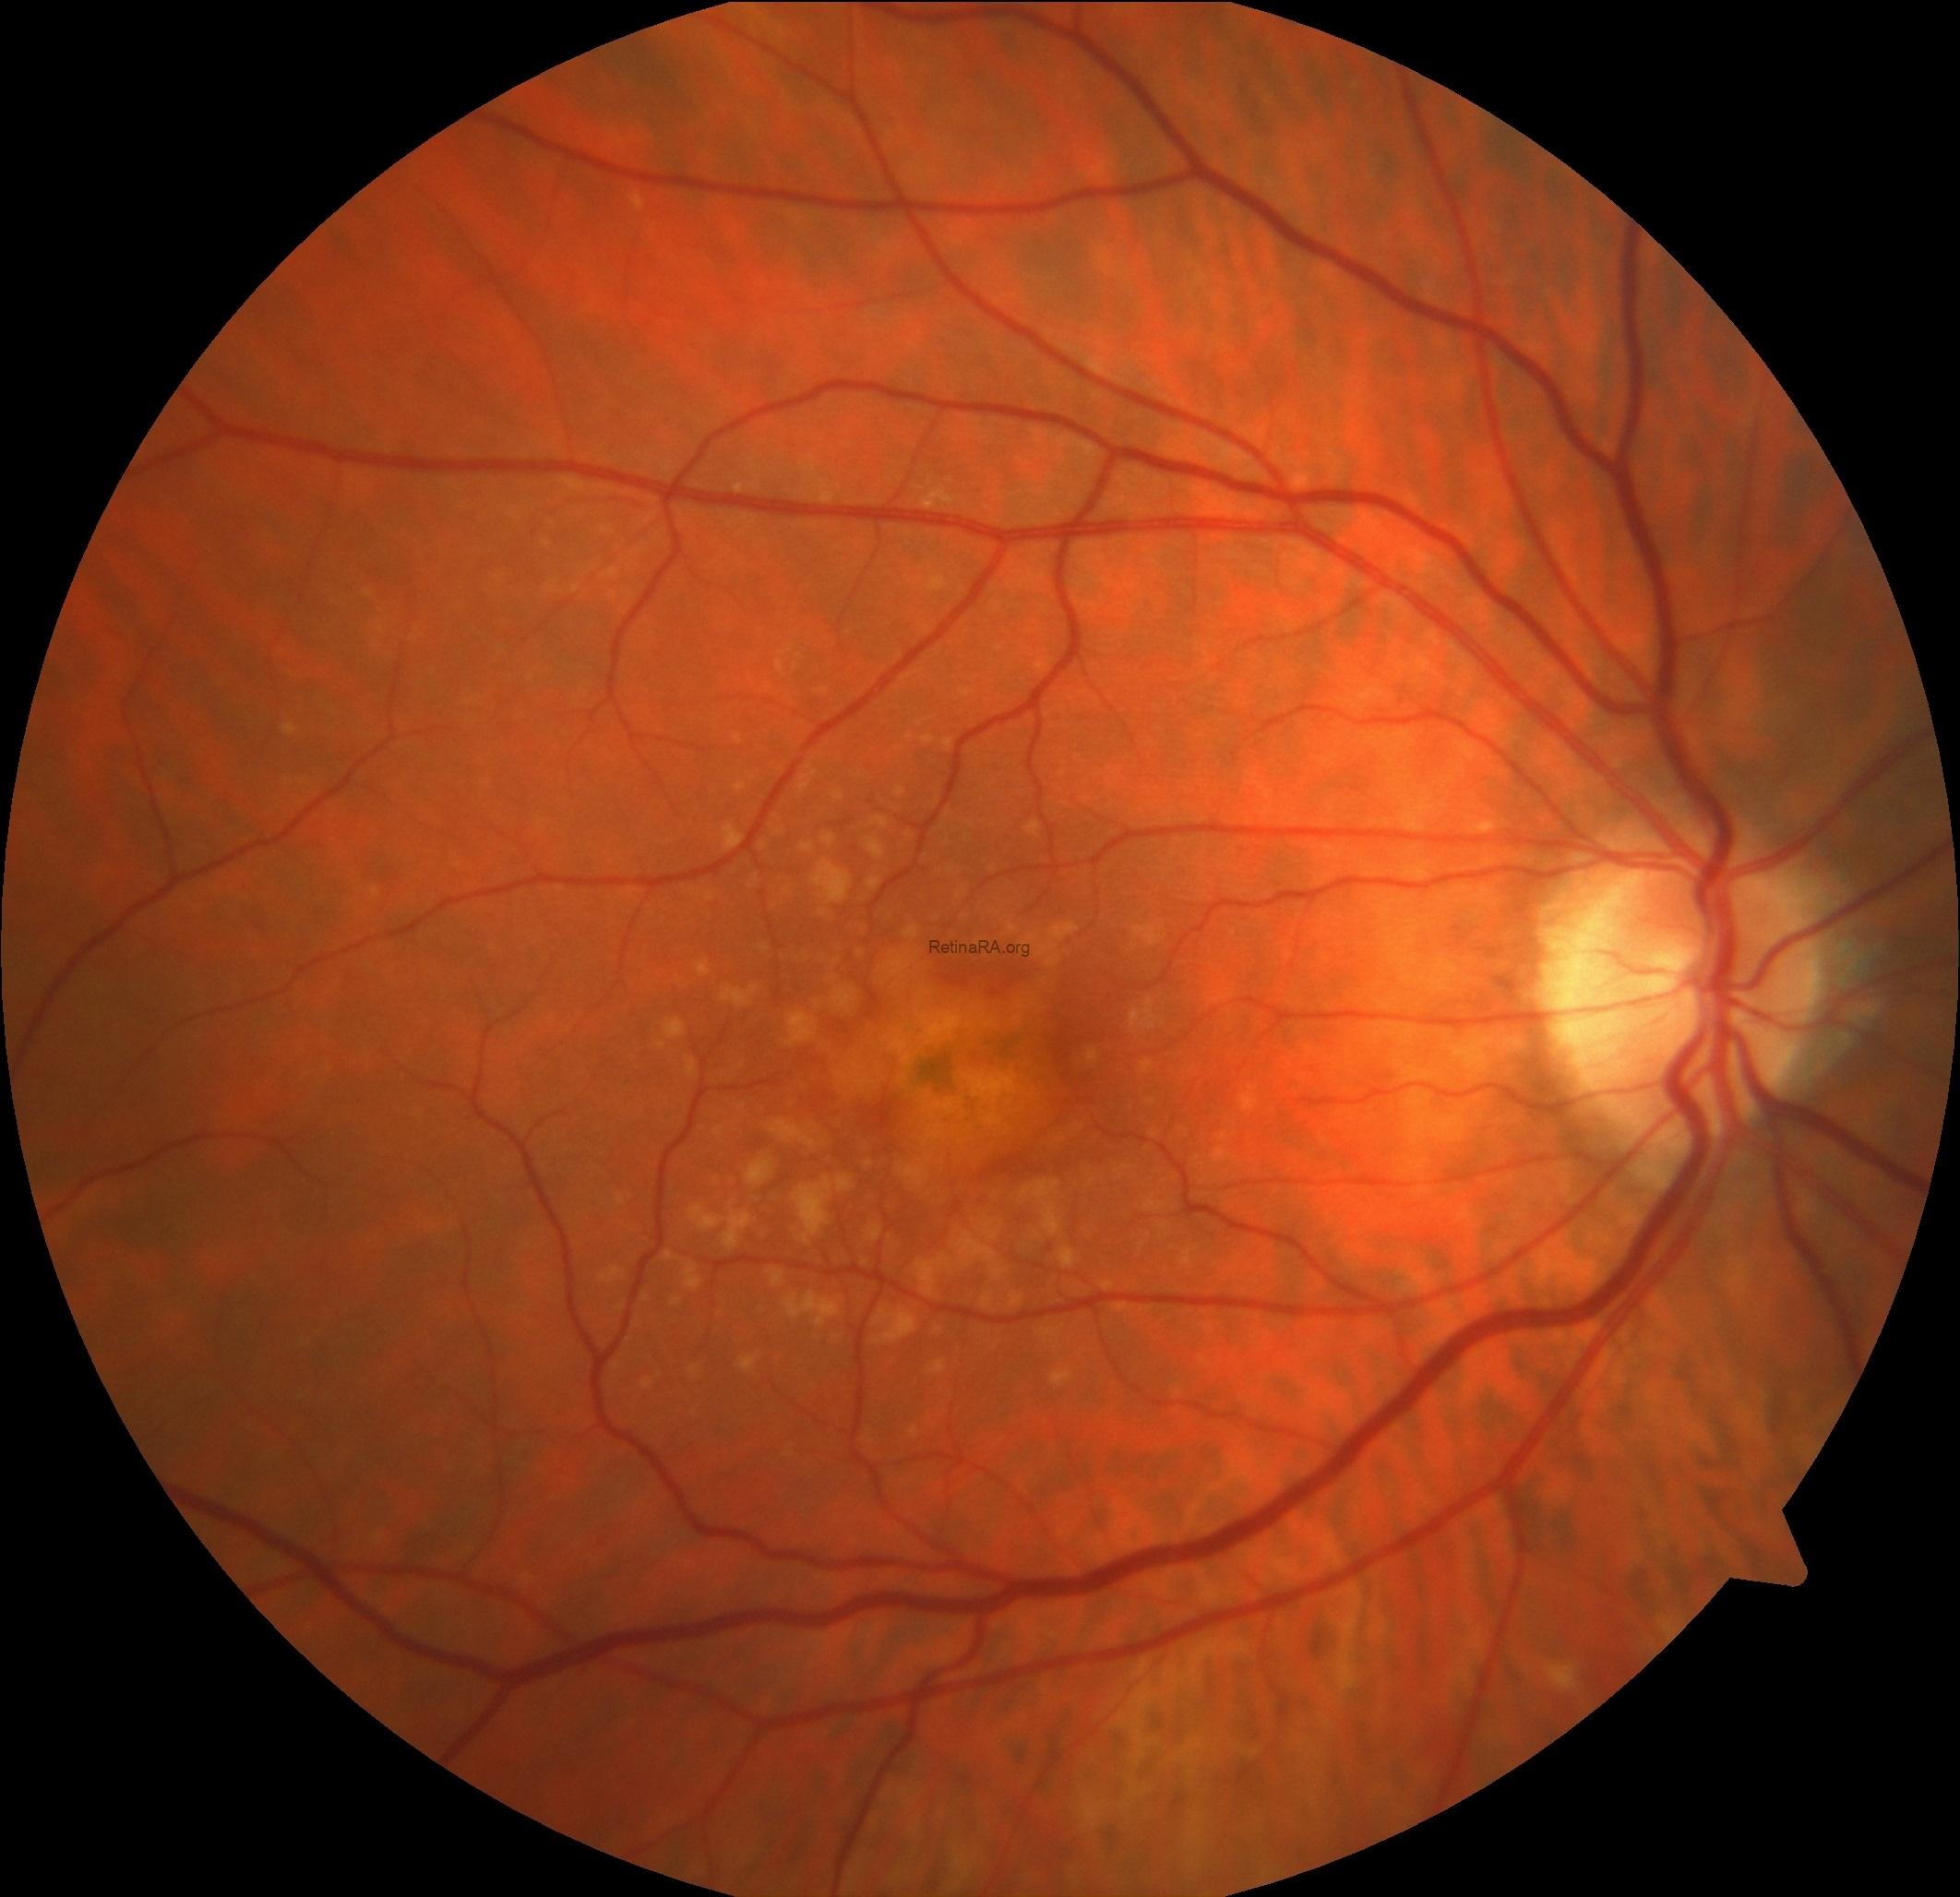

Drusen may grow and coalesce to form drusenoid pigment epithelial detachment (PED). Although there is no definitively accepted value, drusen larger than 350 microns have been accepted as drusenoid PED in some clinical studies. On color fundus photography, the Drusenoid PED appears as a large yellow, raised area above the surface. RPE proliferation may accompany. OCT provides a definitive diagnosis of drusenoid PED. Note that hyperreflectivity of drusen and drusenoid PED are same. RPE proliferation, seen as a gray-brown area within the drusenoid PED on color photography, is observed as a hyperreflective formation at the level of the RPE causing shadowing underneath on OCT.

Color photography of drusenoid PED